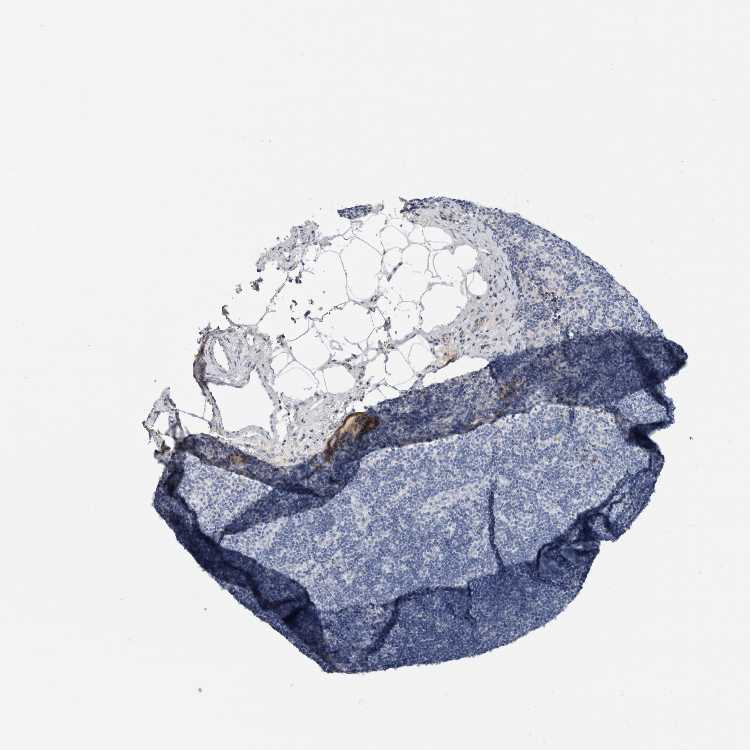

TISSUE PRIMARY DATA LYMPH NODE Show tissue menu

Lymph node

LYMPH NODE - Antibody stainingi

Antibody staining in the annotated cell types in the current human tissue is reported as not detected, low, medium, or high, based on conventional immunohistochemistry profiling in selected tissues. This score is based on the combination of the staining intensity and fraction of stained cells.

Each image is clickable and will lead to virtual microscopy that enables deeper exploration of all samples and also displays staining intensity scores, fraction scores and subcellular localization as well as patient and tissue information for each sample.

Antibody HPA031828Antibody CAB025686

Germinal center cells Not detectedNot detected

Non-germinal center cells Not detectedNot detected